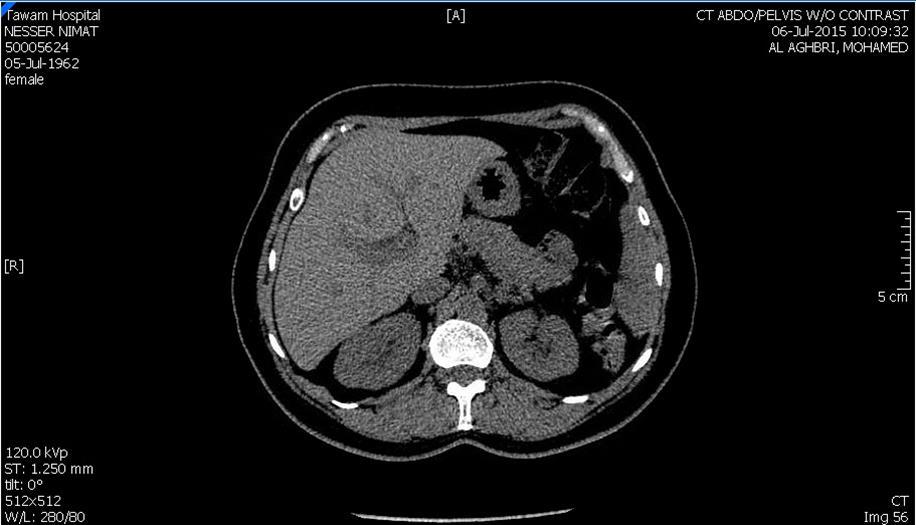

Blood tests on April 14th showed: Na = 131, K = 5.1, Urea = 6.9, S. Creatinine = 96, and eGFR = 61ml/min. Urine analysis and cultures confirmed E. coli urosepsis, blood cultures were negative. Renal US revealed echogenic kidneys, mild bilateral hydronephrosis of about 12 mm with normal ureters and urinary bladder (Figure 1 and Figure 2). Treatment with oral antibiotics resulted in improvement of temperature and dysuria. On April 20th patient seen by endocrinology and nephrology because of persistent back pain, dapagliflozin was discontinued and followed by resolution of symptoms in few days. Patient had two kidney ultrasounds in May and June, both indicated gradual resolution of bilateral hydronephrosis. Repeat CT of the abdomen on July 7th revealed complete resolution of hydronephrosis (Figure 3). Most recent eGFR is 72 ml/min.

Figure 3.CT Scan showing bilateral kidneys with no hydronephrosis